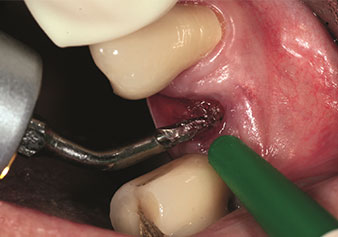

W&H also offers the perfect solution for the internal sinus lift.

Following preparation of the maxillary sinuses with the corresponding instrument set (Fig. 3), the new Z35P instrument (Fig. 4) is used to lift the membrane hydrodynamically. The same instrument set can also be used for piezosurgical preparation of the implant bed in increasing diameters (Figures 3 and 4 included with the kind permission of Dr Mario Kirste, Frankfurt/Oder).